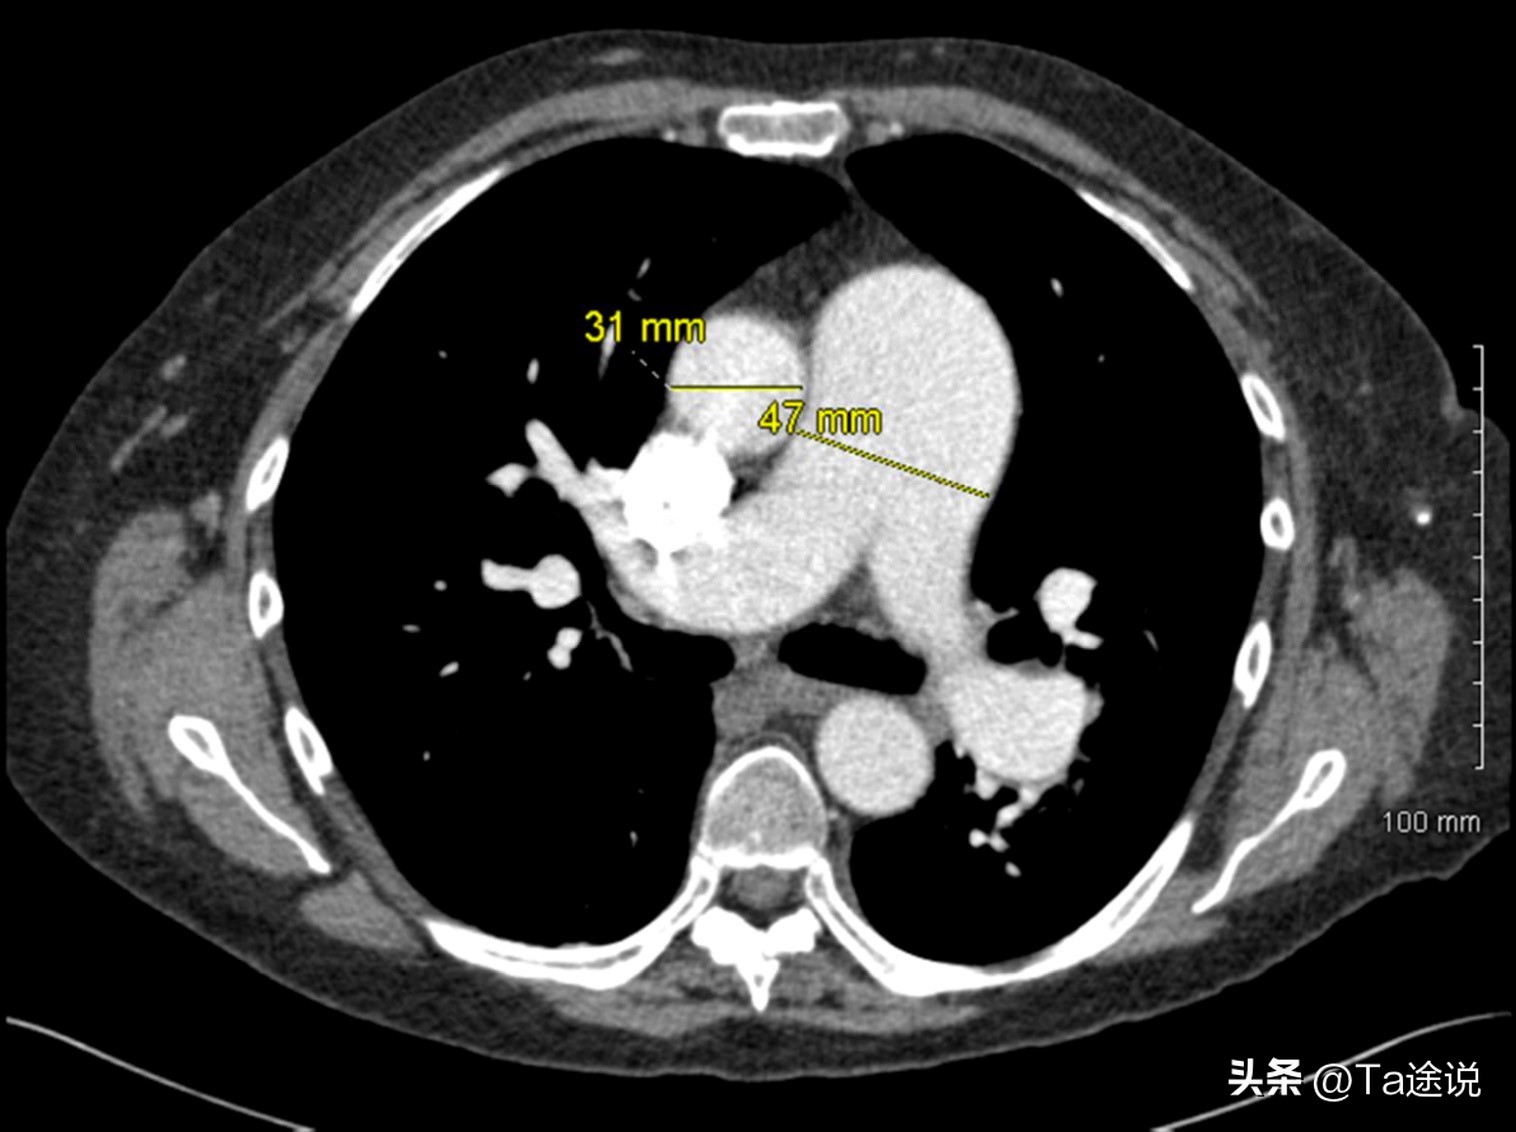

肺动脉高压CT图

“根据化验结果显示,您患有严重的肺动脉高压,而这种病症很有可能是先天性心脏病引发的,建议您去专业医院再次进行检查...”医生不敢妄下定论,但结果却不容乐观。

鉴于医生诊断的棱模两可,吴梦不愿接受现实,她没过几天就赶往北京的专业医院,可又一次的检查结果表示:这不是误诊!而且吴梦的已经没有几年可活。